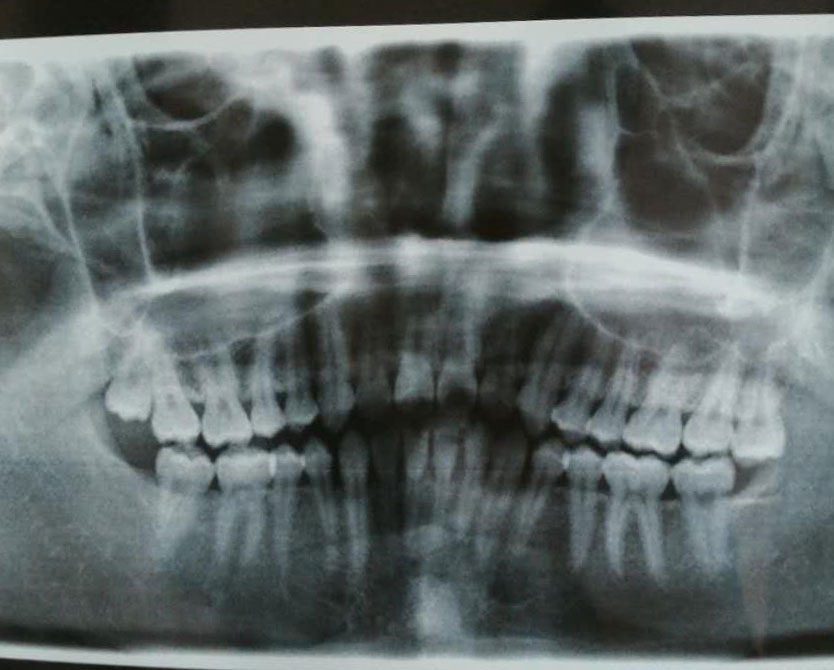

因为最近感觉牙槽最深处长了一颗智齿,而且很歪,于是今天就去拍了张牙片,牙片如下:

可以看到图像左上角两颗牙呈现了V字形。

牙片左上角的智齿应该就是图片2的情况了。

然后可以看到牙片右上角其实也长了一颗智齿,这种智齿则属于图片3的情况。

这种智齿如果下排也长了对应的智齿,而且能够咬合的话也是可以不用处理,但是我下排并没有智齿,所以医生推荐我拔了。

因为如果不拔的话,由于缺少下排的牙齿会使得牙齿慢慢变长最终不断摩擦下方的口腔组织,最终导致下方的组织发炎红肿。

不过医生说就目前来看两颗智齿都还可以先观察一阵子,如果有什么不适感了再来拔。